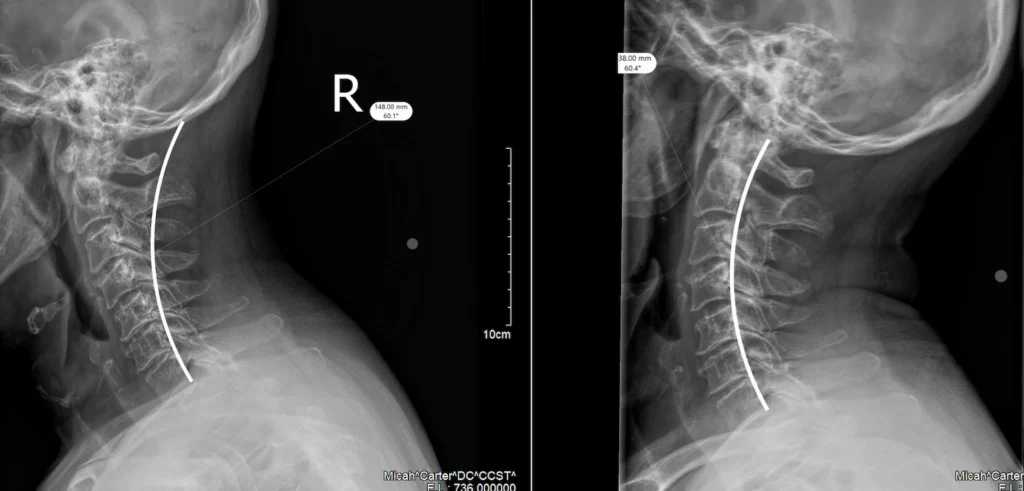

Before any treatment begins, Dr. Carter conducts a comprehensive examination. This includes taking on-site digital X-rays, assessing range of motion, identifying areas of tenderness and inflammation, and understanding exactly how the accident occurred. The mechanism of injury matters because it tells us where to look for problems.

When a collision forces your head forward and backward rapidly, the vertebrae in your cervical spine can shift out of their normal position. These misalignments put pressure on nerves, restrict movement, and cause pain.

Chiropractic adjustments gently restore proper alignment. This reduces nerve interference, allows damaged tissues to heal more efficiently, and helps restore normal range of motion. The adjustments themselves are precise and controlled. Patients often feel relief after just a few sessions, though full recovery depends on the severity of the injury.